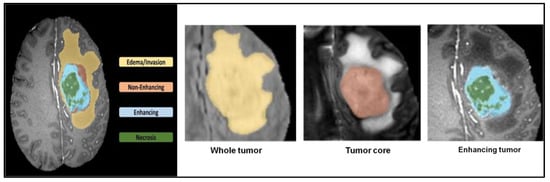

- 1251 patients’ 3D MRI datasets were gathered from the BraTS dataset in the research.

5.1. Dataset